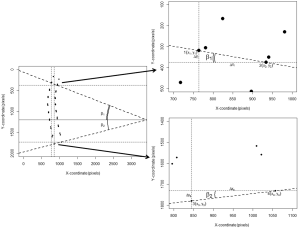

The Cobb’s kyphosis angle was calculated from the raw coordinates by the formula: α=β1+β2 = arctan(∆yI/∆xI) + arctan(∆yII/∆xII) = arctan[(y1–y2)/(x1–x2)] + arctan[(y3–y4)/(x3–x4)] (Figure 2). We computed the Pearson’s correlation coefficient r and corresponding t-test statistic between the calculations derived from the SpineAnalyzer® software and the manual measurements for the Cobb’s kyphosis angle. In addition, the intraclass correlation coefficient (two way mixed, consistency and agreement) with the matching F-test statistic was determined and classified according to Landis and Koch (20). Finally, we evaluated if the differences between measurements was different from 0 by a t-test and mapped the results in a Bland-Altman plot including calculation of the interval between the 95% limits of agreement by taking the mean difference plus and minus 2 standard deviations (21) to further evaluate the agreement between the measurements. SPSS statistics software version 20 (IBM, Armonk, NY, USA) and R software version 3.0.1 (R Foundation for Statistical Computing, Vienna, Austria) were used for the analyses.